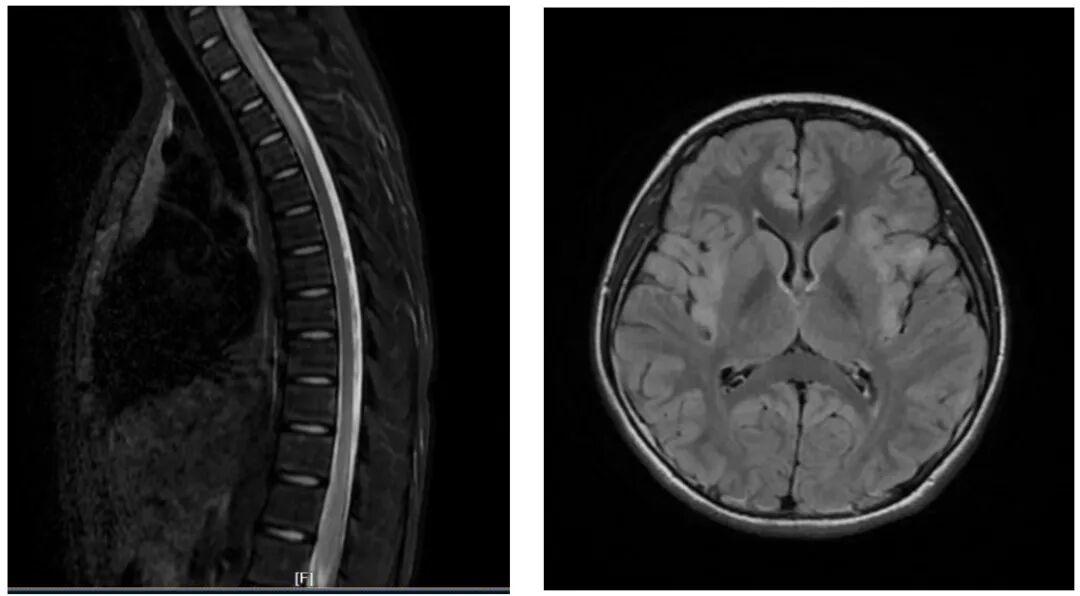

神经内科专家经详细问诊、查体后,当即决定将双双收入院,并安排了血液检查、腰椎穿刺、头颅 + 全脊髓磁共振等一系列检查。最终明确诊断,双双患有中枢神经系统脱髓鞘病。

可能很多家长对这个疾病感到陌生,简单来说,它是一组由自身免疫介导的疾病,主要影响中枢神经系统的白质。我们可以把神经比作“电线”,而髓鞘就是包裹在电线外面的“绝缘层”,当髓鞘受损(脱髓鞘),神经信号的传导就会受到影响,从而引发各种症状。

这类疾病可分为急性播散性脑脊髓炎、MOG 抗体相关疾病、视神经脊髓炎谱系疾病、多发性硬化等不同类型。其临床表现十分复杂多样,常见的有眼痛、视力下降、癫痫、头晕头痛、肢体无力、感觉麻木、二便障碍等,严重时还可能出现意识障碍、呼吸衰竭,甚至危及生命,或遗留严重的神经系统后遗症。

儿童中枢神经系统脱髓鞘病的治疗核心是“早发现、早诊断、早治疗”,分为急性期和缓解期两个阶段:急性期需要早期、规范的治疗,一旦延误,可能导致视力下降、运动障碍、认知障碍等残障,还可能继发癫痫;缓解期则需要长期口服药物,并定期到门诊复查,目的是预防疾病复发,保护孩子的神经系统功能。

双双的病情属于起病急、进展快、病情重的类型,若不及时干预,很可能危及生命并留下终身后遗症。明确诊断后,神经内科团队立即启动治疗。经过积极救治,双双的肢体麻木症状已完全消失,肢体无力明显好转,目前已能短距离独立行走,正在逐步康复中。